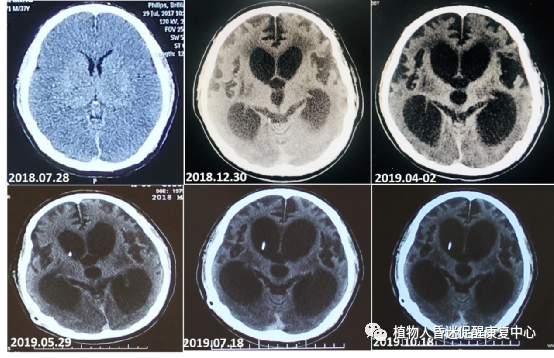

图2:患者心跳呼吸骤停后缺血缺氧性脑损伤导致脑萎缩伴有脑室进行性扩大,患者从2018.07.28日发病脑室进行性扩张,只是一种萎缩性的扩张,不是脑积水,因此尽管行脑室-腹腔分流脑室仍然在扩张,没有效果,大家要引以为鉴。